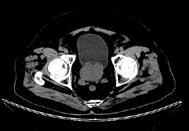

问题 男,65岁,尿频尿急及排尿困难,CT检查如图所示,下列说法错误的是 ( )

选项 A、此为前列腺增生 B、此为前列腺癌 C、其包膜光滑,境界清晰 D、与膀胱分界清楚 E、前列腺形态呈类圆形

答案 B